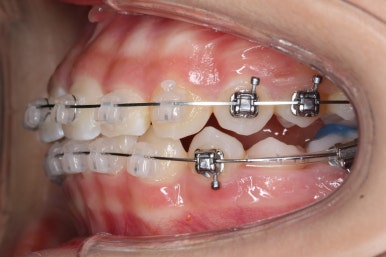

예상한대로 자리만 충분히 마련해주니 그동안 나오지 못하고 막혀있던 치아가 슬그머니 고개를 내밀고 있습니다.

좀 더 기다렸다가 좀 더 올라오면 장치를 부착해서 정리해주기만 하면 되겠습니다.

부산치아교정잘하는곳 키다리아저씨치과에서는 치아가 올라오자마자 장치를 부착하여 가지런하게 해줍니다. 이제 어느 정도 큰 그림은 그려졌다고 보시면 되겠습니다.

어느 정도 큰 그림이 그려졌으면 중앙선이라든지 치아의 디테일한 면을 더 수정하고 마무리하게 되겠습니다.